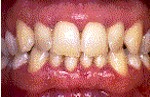

g) Etapas de la Enfermedad Periodontal

Se resume las etapas de la progresión de la enfermedad y su asociación con los signos y síntomas.

Salud.- Color rosa coral, la encía rodea firmemente al diente, no sangran.

Gingivitis.- Sangrado al cepillado o al sondaje, encías inflamadas y sensibles, posible mal aliento y gusto.

Periodontitis Leve.- Sangrado más pronunciado e hinchazón en las encías, las encías comienzan a despegarse de los dientes, mal aliento y gusto, bolsas de 3-4 mm de profundidad.